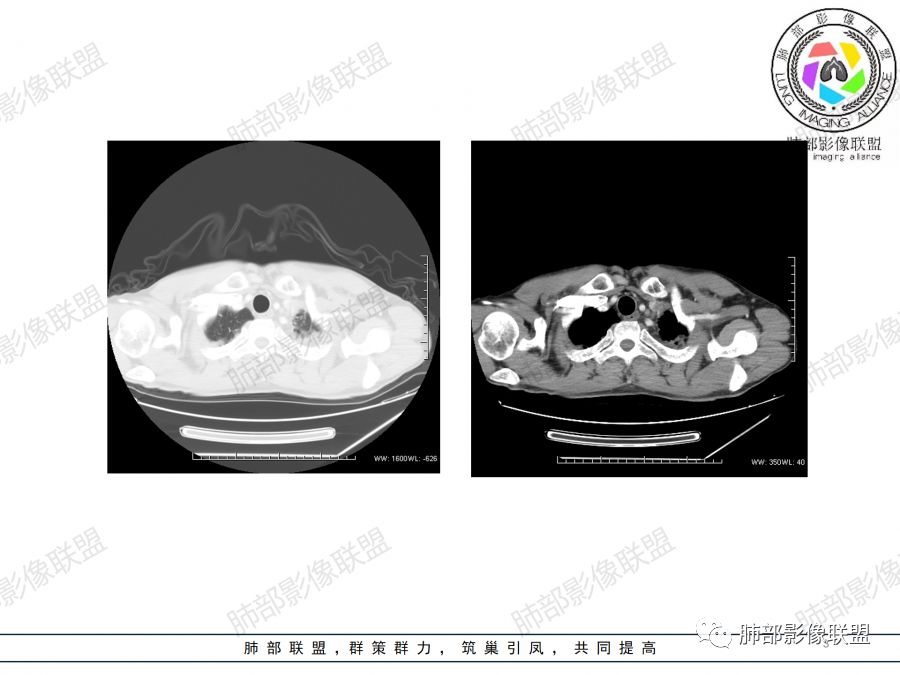

左上肺占位支气管阻塞伴肺不张、肿瘤不均匀强化,考虑鳞癌.

左肺上叶见实性结节,边缘可见分叶,周周可见磨玻璃影,病灶不均匀强化,中心可见坏死,部分坏死边界不清,部分呈环形,血管进入病灶内部,边缘逐渐变细截断,总体表现考虑恶性,腺癌。

中年男性,咳嗽咳痰一月。左肺上叶团块状软组织密度影,边缘部分清晰周围见磨玻璃影,增强后其内密度不均可见散在斑片状低密度区,血管造影征完整,团块邻近胸膜可见多发圆形低密度透光灶。左肺门处上叶血管似被包绕。左侧胸膜粘连肥厚。考虑1.左肺占位,淋巴瘤?鳞癌?2.因病灶内散在低密度待除外感染性病变可能

中年男性,咳嗽咳痰一月余入院胸CT:左肺上叶前段占位性病变,病灶内可见密度不均,可见低密度区,病灶可见分叶,增强病灶内可见血管征,血管边缘模糊,病灶近胸膜下呈膨胀性生长。诊断考虑:恶性病变。

40岁以上男性,中等病程,咳嗽,咳痰,左上块影,孤立,膨胀,胸膜受累,内密度高低不一,血管穿入,考虑肺癌,鳞?气管镜or穿刺!

左肺上叶肿块,强化不均匀,内见坏死,血管纤细,病灶周围有阻塞性炎,所见图像未见肿大淋巴结。考虑鳞癌可能大。

中年男性,亚急性起病,咳嗽,咳痰,左肺上叶肿块,边界清,膨隆,可见分叶,增强可见内部坏死,不均匀强化,部分边界累及胸膜,考虑恶性。

左肺上叶肿块,周周可见磨玻璃影,不均匀强化,内部可见坏死,部分坏死边界不清,血管进入病灶内,恶性肿瘤,考虑鳞癌。

分叶,破坏力不强,纵隔胸膜受累,周围阻塞性炎症,胸膜多发结节。考虑恶性,支持腺癌可能大。

左肺上叶肿块,边缘大部分平直,部分膨隆,周周可见磨玻璃影,不均匀强化,内部可见坏死,部分坏死边界不清,考虑恶性肿瘤,鳞癌可能大,病灶边缘大部分平直,不除外炎性。

患者中年男性,咳嗽、咳痰1月余入院。胸部CT:左肺上叶尖段近胸膜下肿块占位灶,边缘光滑,边界清楚,周围可见片状磨玻璃影,可见平直、毛刺、分叶征象,增强轻度强化,内可见点片多发低密度区及部分血管影,与支气管关系欠清,左肺上叶背侧胸膜增厚、胸膜下结节,右肺似见多发小结节灶,淋巴结不大。综合考虑良性病变,结核可能性大,鉴别腺癌并肺内、胸膜转移及淋巴瘤等。